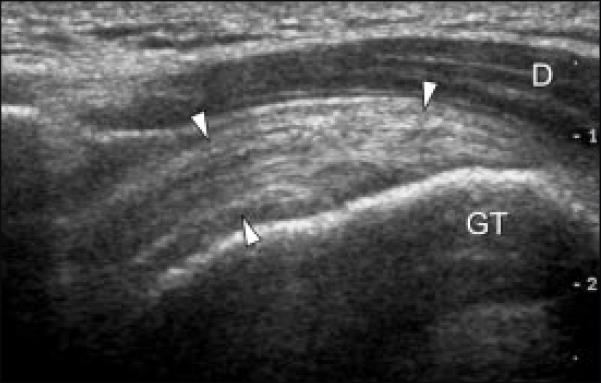

These changes are visible in an ultrasound scan.

Second, diagnose properly. With an ultrasound scan you can detect the problem.